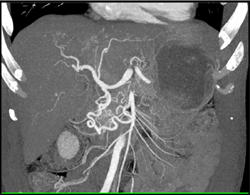

Dense Liver Due to Amiodarone